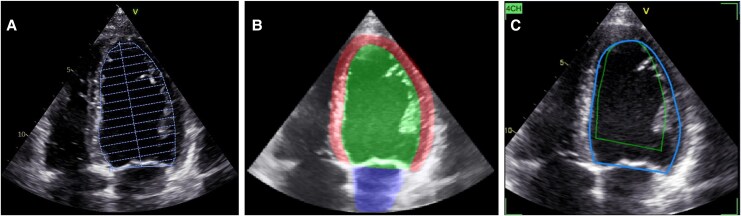

Aims: The low reproducibility of echocardiographic measurements challenges the identification of subtle changes in left ventricular (LV) function. Deep learning (DL) methods enable real-time analysis of acquisitions and may improve echocardiography. The aim of this study was to evaluate the impact of DL-based guidance and automated measurements on the reproducibility of LV global longitudinal strain (GLS), end-diastolic (EDV) and end-systolic (ESV) volume, and ejection fraction (EF).

Methods and results: Forty-six patients (24 breast cancer and 22 general cardiology patients) were included and underwent four consecutive echocardiograms. Six were included twice, totalling 52 inclusions and 208 echocardiograms. One sonographer-cardiologist pair used DL guidance and measurements (DL group), while another did not use DL tools and performed manual measurements (manual group). DL group recordings were also measured using a commercially available DL-based EF tool. For GLS, the DL group had a 30% lower test-retest variability than the manual group (minimal detectable change 2.0 vs. 2.9, P = 0.036). LV volumes had ∼40% lower minimal detectable changes in the DL group vs. the manual group (32 mL vs. 52 mL for EDV and 18 mL vs. 32 mL for ESV, P ≤ 0.006). This did not translate to a significant improvement in EF reproducibility in the DL group. The benchmarking method showed similar results compared with the manual group.

Conclusion: Combining real-time DL guidance with automated measurements improved the reproducibility of LV size and function measurements compared with usual care, but future studies are needed to evaluate its clinical effect.